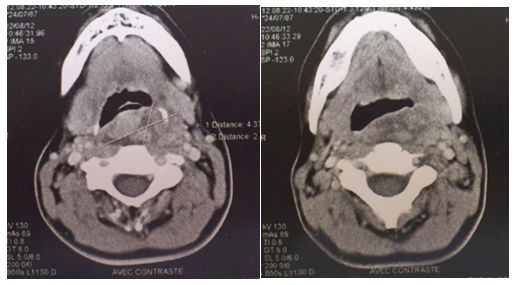

A 23-year-old female, with no relevant medical history, presented to the ENT out patient clinic for neck pain and left otalgia for the past 1 year, dysphagia for solids, snoring and dysphonia for the past 4months. Her general state was marked by significant weight loss. Clinical examination found a bulging of the left posterolateral wall of the pharynx with a regular mucosa. (Figure 1) There were no paralysis of cranial nerves nor abnormalities at otoscopy. Cervico-facial CT scan show a heterogeneous mass of the left parapharyngeal and retropharyngeal spaces of the oro and hypopharynx, measuring 6cm of diameter evoking a necrotic tumor (Figure 2). Endoscopy of the upper aero-digestive ways revealed a regular bulging with an intact mucosa of the posterolateral wall of the oro and hypopharynx with no laryngeal involvement. Deep biopsy -after incision of the mucosa- revealed a monophasic mesenchymal proliferation composed mainly of uniform spindle cells forming interlacing fascicles which was consistent with synovial sarcoma after immunohistochemistry: positive for anti-CD99, anti-bcl and Anti-vimentin, negative for anti-PS 100, anti-cytokeratin, anti-desmin and anti-CD34. Extension work up including chest CT scan, abdominal ultrasonography and bone scintigraphy have not found any distant metastases. The patient underwent a chemotherapy pending for radiotherapy according to the multidisciplinary ENT-Oncology staff decision. After the 2nd cure of chemotherapy, the patient presented respiratory symptoms that prompted a chest CT scan showing multiple pulmonary metastases. Patient then underwent a palliative chemotherapy.

Figure 2 Cervico-facial CT scan-axial section: heterogeneous mass of the left parapharyngeal and retropharyngeal spaces of the oro and hypopharynx.